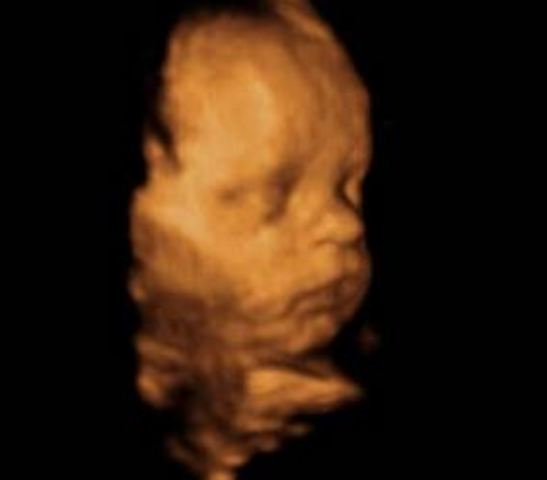

En la semana 14 de embarazo, las orejas del feto se encuentran implantadas a ambos lados de la cabeza y también los ojos se han acercado; es decir, el bebé tiene ya una carita casi perfecta, tanto que ya se distingue el puente de la nariz. Incluso se puede ver que hace algunos pequeños gestos. Además, el cuello se ha alargado y el mentón ya no descansa sobre el pecho. Ya no parece que esté enroscado.

• Semana 15